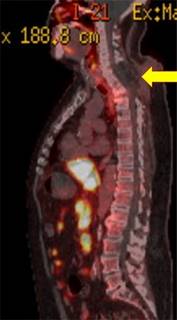

A 72-year-old male patient who underwent wide laminectomy surgery from C7 to T4 level without arthrodesis, due to a history of secondary metastatic disease of prostate cancer performed in an external institution (Figure 1). During that hospitalization he presented fever which was managed with intravenous antibiotics for four weeks. Four months postoperatively he was admitted to our hospital due to kyphosis deformity and decreased strength in the lower extremities. The patient has coronary revascularization surgery as an important background.

Figure 1: Panoramic sagittal view of CT scan. Yellow arrow indicates extensive laminectomy without instrumentation.